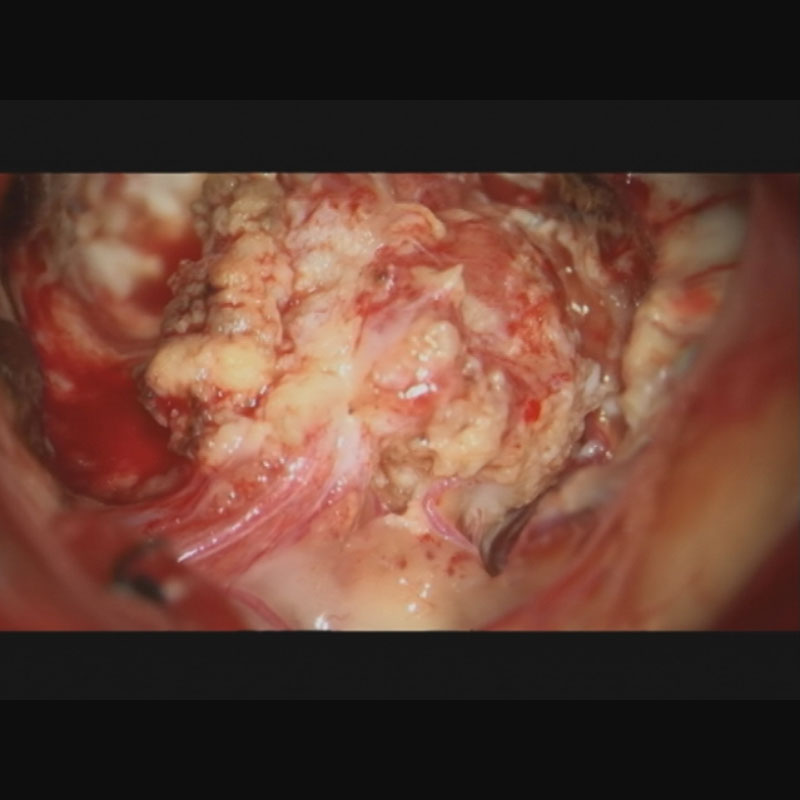

412

'23年5月

20代

小脳血管芽腫

頭蓋内腫瘍摘出術

No.’23_46 手術前1

No.’23_46 手術前2

No.’23_46 摘出 前

No.’23_46  摘出 中

No.’23_46 摘出 後